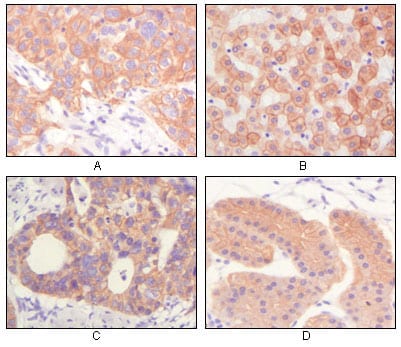

分类: 科研抗体货号: 20341别名: CD28LG; LAB7; B7.1应用: IHC,IF反应种属: Human

分类: 科研抗体货号: 20340别名: hWNT5A;应用: IHC反应种属: Human

分类: 科研抗体货号: 20338别名: LFS1, TRP53, TP53应用: WB,IHC反应种属: Human

分类: 科研抗体货号: 20354别名: KIA; Ki-67; MKI67应用: IHC,IF反应种属: Human,Mouse,Rat,Rabbit,Monkey